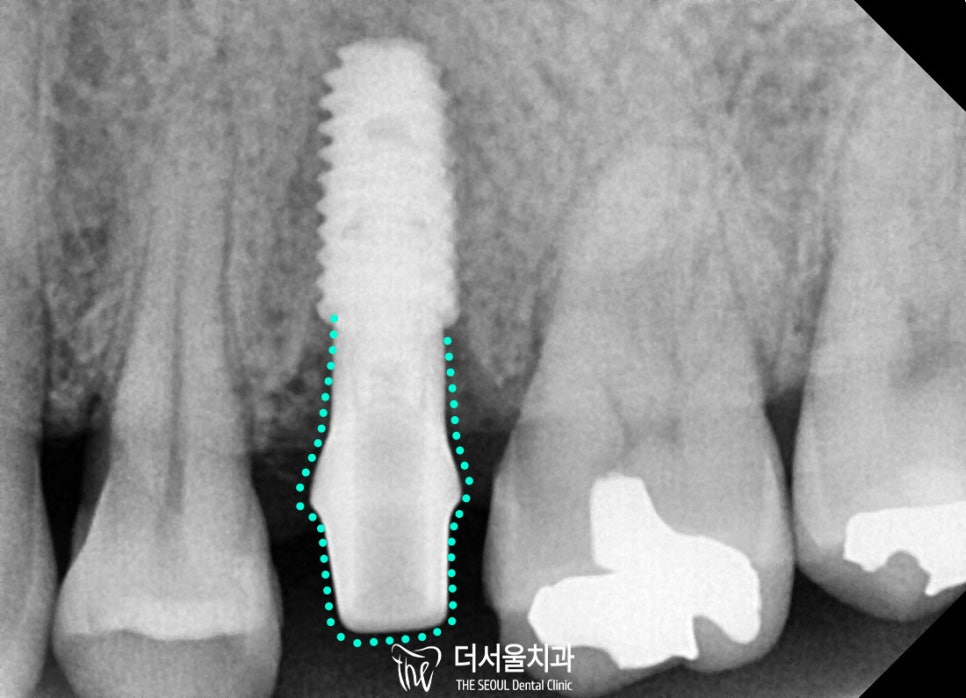

부러진 치근을 뽑고

그 자리에 정확하게

픽스처를 심었는데요,

저작력을 잘 버틸 수 있도록

치조골이 튼튼한 곳에

알맞게 식립을 진행해 드렸습니다.

잇몸뼈의 너무 바깥쪽도 아니고

너무 안쪽도 아닌 중앙에 잘 위치 시켰으며

양쪽 치아와의 간격도

잘 맞춰서 심어진게 보이시죠?

성남 치과 에서는

구강 상태에 따라

당일 즉시 식립도 가능하여

이 환자의 경우

2개월 반 만에 고정력도

충분히 확보되었습니다.

그래서 맞춤형 어버트먼트를 제작하고

보철을 올릴 준비까지 되었습니다.